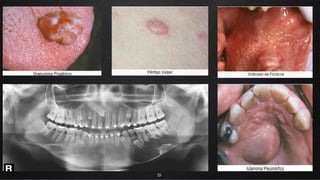

Tipos

Biópsia

Incisional

4.

Excisional